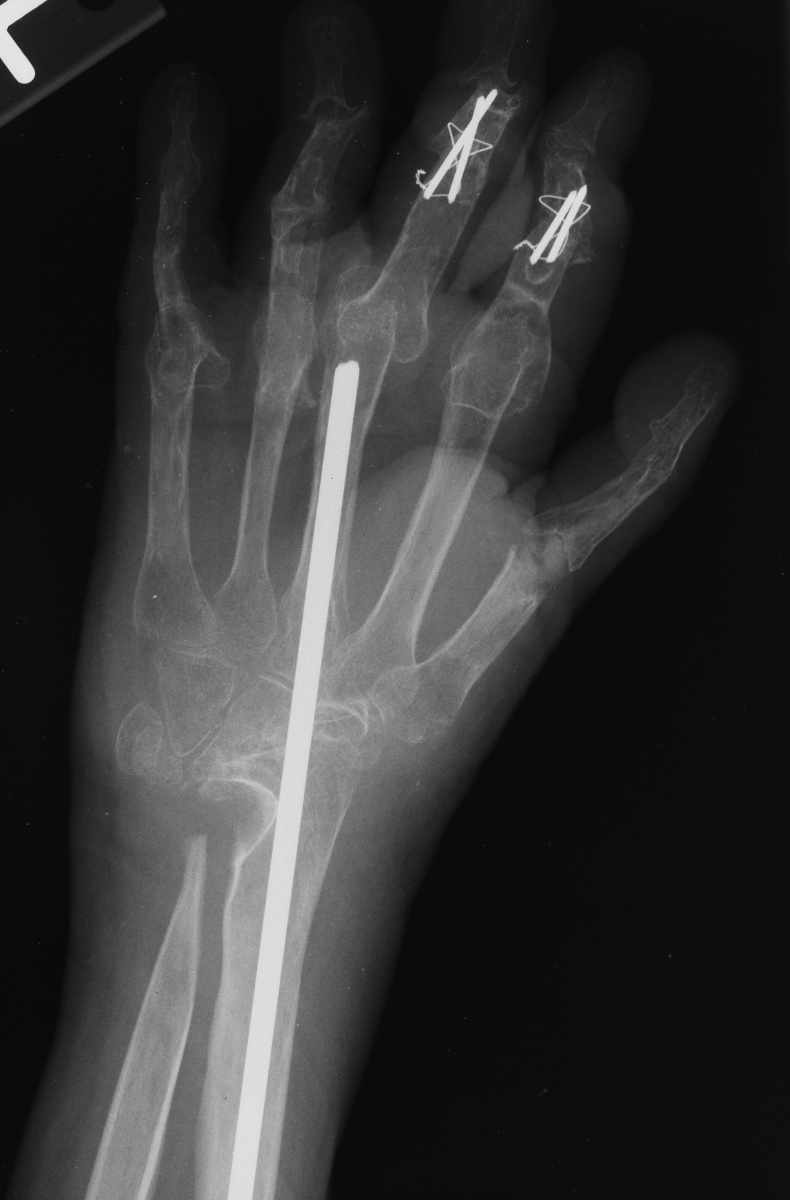

For the second stage of her reconstruction, the index proximal phalanx did not have adequate dorsal cortex to support an implant arthroplasty, and bone graft from the metacarpal head was used to reconstruct this.

Final radiographs, three months postoperative.